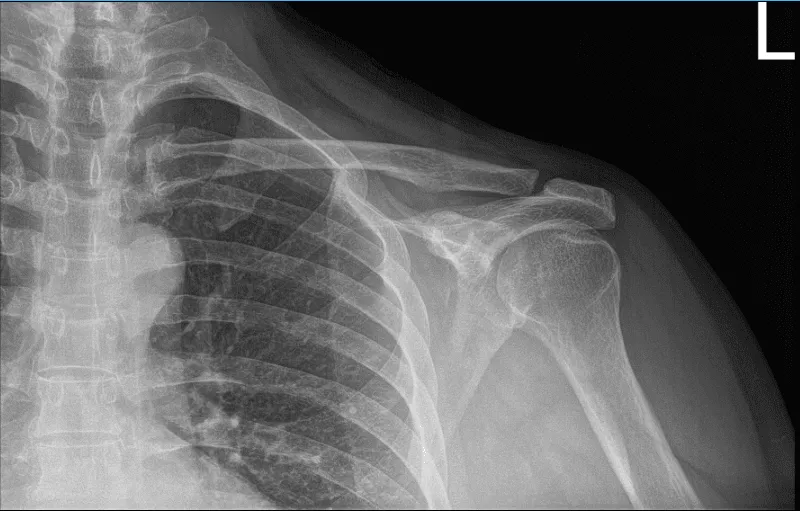

The patient presented today is a 66-year-old, male, and involved in a motor vehicle accident. He complained today about his bilateral shoulders, but the most painful one is his left shoulder. Patient had no shoulder pain prior to the car accident.

He has been doing therapy and it helped marginally. We suspected that the patient had a rotator cuff tear, however his Xray showed normal radiographs. So, we highly recommended that we take an MRI.

His MRI showed clear mild acromioclavicular hypertrophic change. MRI also showed rotator cuff tear of the supraspinatus along with a tear of the long head of biceps.

MRI of left shoulder